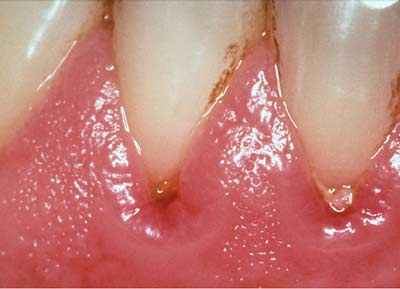

1. Viêm lợi: “báo động đỏ”

Lợi bị đỏ và sưng phồng là tín hiệu báo động khẩn cấp cho những căn bệnh khác nghiêm trọng hơn. Đó là dấu hiệu của sự viêm nhiễm và có thể quá trình viêm nhiễm này sẽ ảnh hưởng đến những bộ phận khác trong cơ thể. Nếu bị viêm lợi thường xuyên thì nguy cơ bị đau tim, mắc các bệnh tim mạch, Alzheimer và sinh non sẽ cao hơn bình thường.

Khi lợi thấy hơi thở có mùi, lợi bị chảy máu hay có mủ, bạn cần đến nha sĩ để kiểm tra ngay. Nha sĩ sẽ làm sạch răng và giải quyết vấn đề viêm nhiễm bằng cách đặt thuốc kháng sinh cục bộ vào những kẽ hở ở lợi tại những nơi bị sưng.